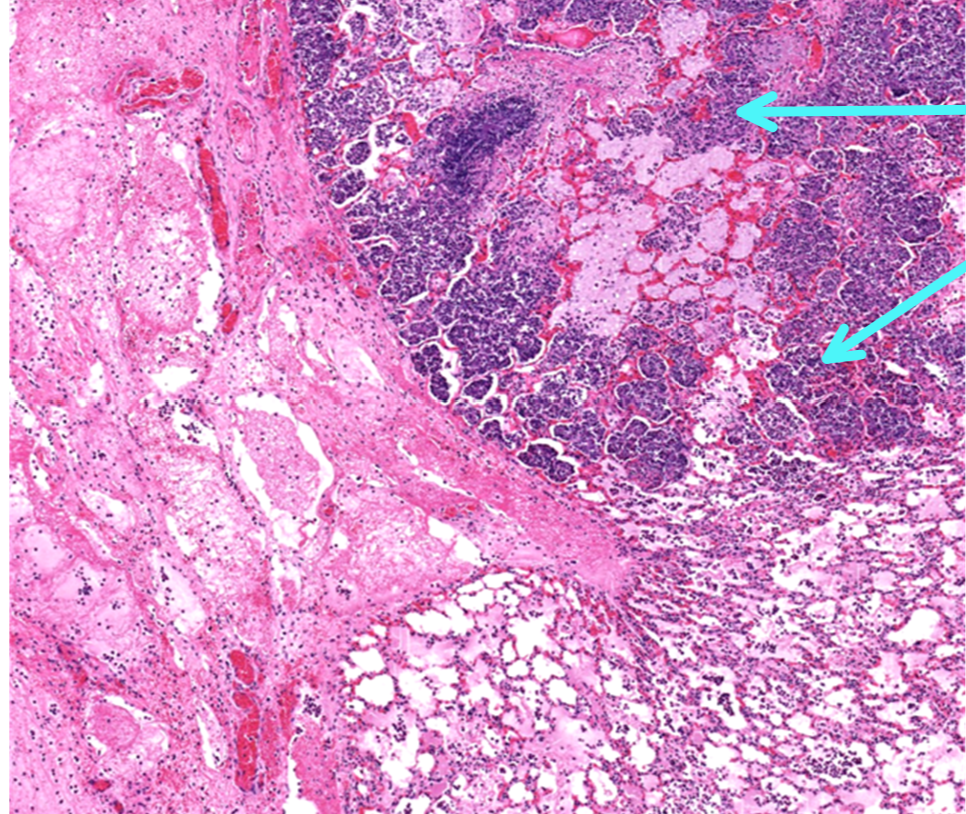

This is from a bovine lung. What is the histomorphologic diagnosis for this lesion?

acute fibrinopurulent bronchopneumonia

Why would this lesion be acute?

because the exudate is predominantly neutrophils and fibrin

Why would this lesion be diffuse?

because most of the section is affected

Why would this lesion be fibrinopurulent?

because of the nature of the exudate